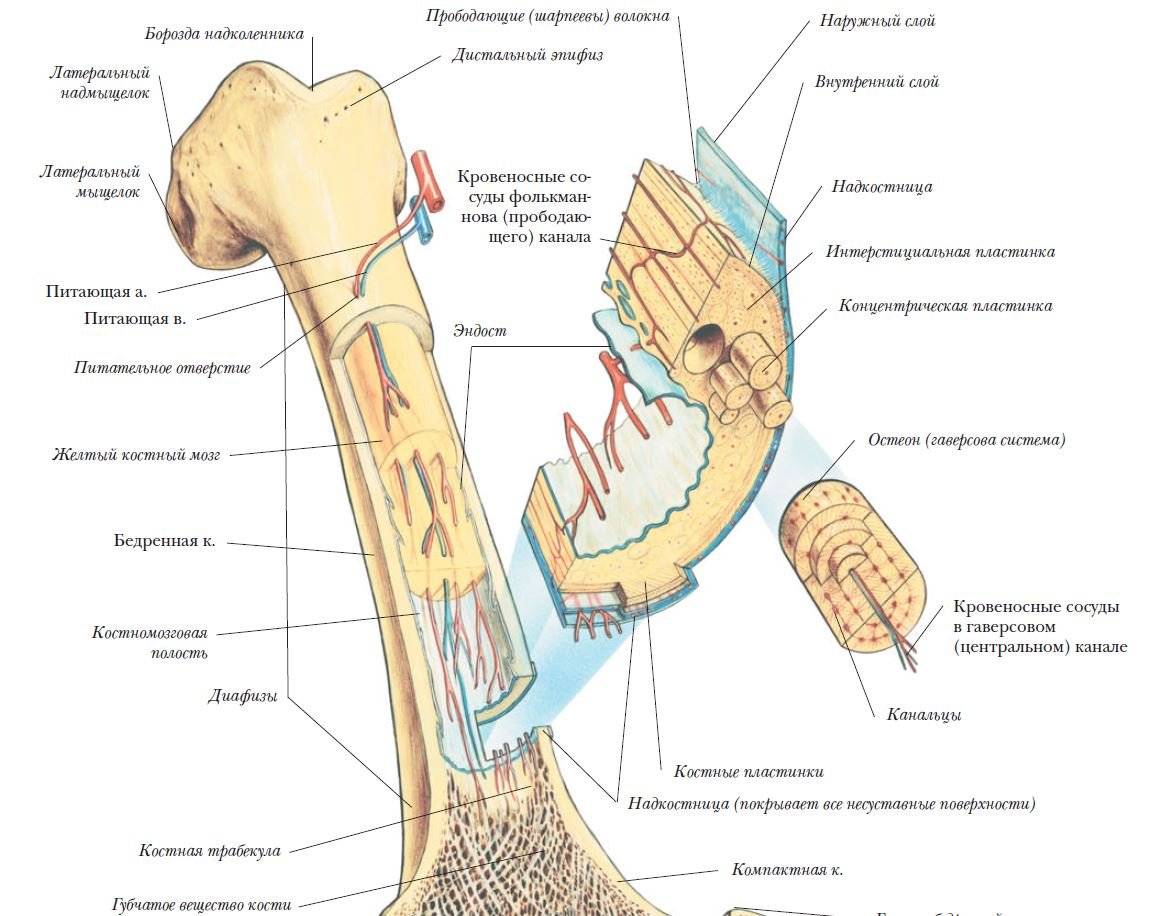

Изучение костного мозга: анатомия и функции

Раздел: Фотогалерея мыслей